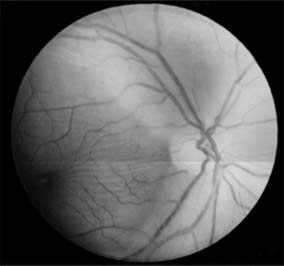

Figure 14-16

Figure 14-16: Atrophic papilledema in a child with a cerebellar medulloblastoma. The disk is pale and slightly elevated and has blurred margins. The white areas surrounding the macula are reflected light from the vitreoretinal interface. The inferior temporal nerve fiber bundles are partially atrophic (arrows).